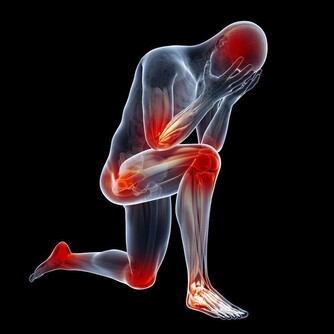

此外,需要注意的是,這4類指標出現異常的人,容易得老年癡呆:同型半胱氨酸、甲狀腺功能、血糖、血脂。